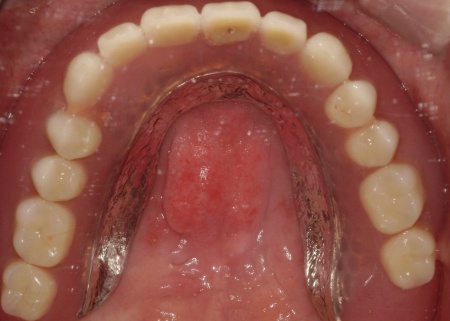

次に、上顎には「インプラント支持型義歯(インプラントオーバーデンチャー)」を金属床義歯で作製します。

金属床にすることで、従来の樹脂製義歯と比べて薄く作ることが可能になり、装着による違和感の軽減が見込めます。

最後に、完成した入れ歯を装着し、噛み合わせや使用感に問題がないことを確認して、治療を終了しています。